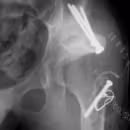

④人工股関節後感染

難治性の人工股関節置換術後感染に対し、抗生剤入りセメントモールドを使用した二期的再建術を行い、股関節機能を再建します。